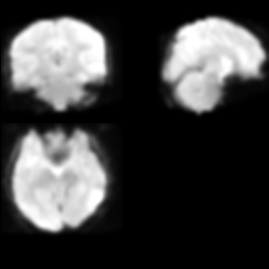

The SPM results of ADHD200

Could you please post a sample of the preprocessed image of ADHD200 fMRI image?